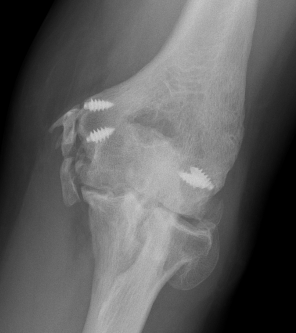

CT

Define anatomical location of the HO prior to surgical excision

- 56 elbows with post fracture HO

- 3D dimensional CT scans

- medial capsule 93%, lateral capsule 80%

- medial supracondylar 57%

- lateral supracondylar, radial head ulnar region 50%